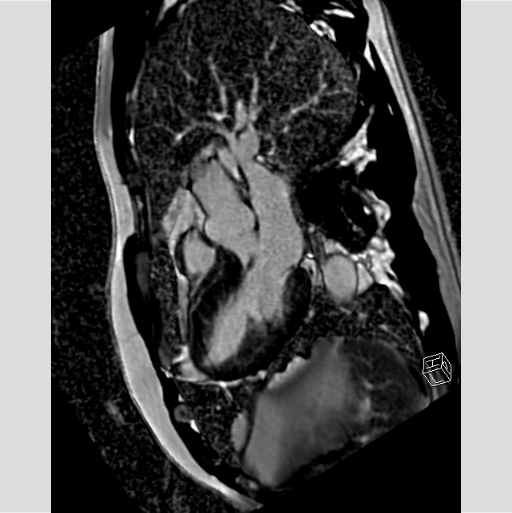

閉塞性肥大型心筋症の心臓に経皮的中隔心筋焼灼術 (PTSMA)を施した画像ですが、MRIでは造影剤を用いる事なく心臓の動きを捉えることができるだけでなく、エタノールにより壊死させた中隔心筋を明瞭に描画することができるので治療効果の判定に有用です。

PTSMA前